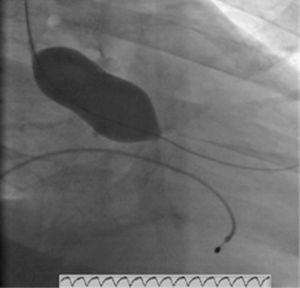

Atendendo ao quadro de instabilidade hemodinâmica com choque cardiogénico, foi decidida a realização de valvuloplastia aórtica (Figura 3) com balão NUCLEUS 20mm, sob ritmo de pacing a 220 bpm, verificando-se uma redução do gradiente de 97 para 46mmHg. Ao mesmo tempo, foi feita revascularização miocárdica completa com colocação de dois stents sem fármaco. A aortografia revelou insuficiência aórtica moderada, pelo que se optou pela não colocação de balão intra-aórtico.

O doente teve alta ao 24.° dia de internamento, em classe NYHA II. No ecocardiograma transtorácico à data de alta apresentava compromisso moderado a grave da FSG (Figura 4), gradiente valvular aórtico médio de 31mmHg e área valvular de 1,06cm2. Programou-se cirurgia cardíaca, após cumprimento de um mês de dupla antiagregação plaquetar.